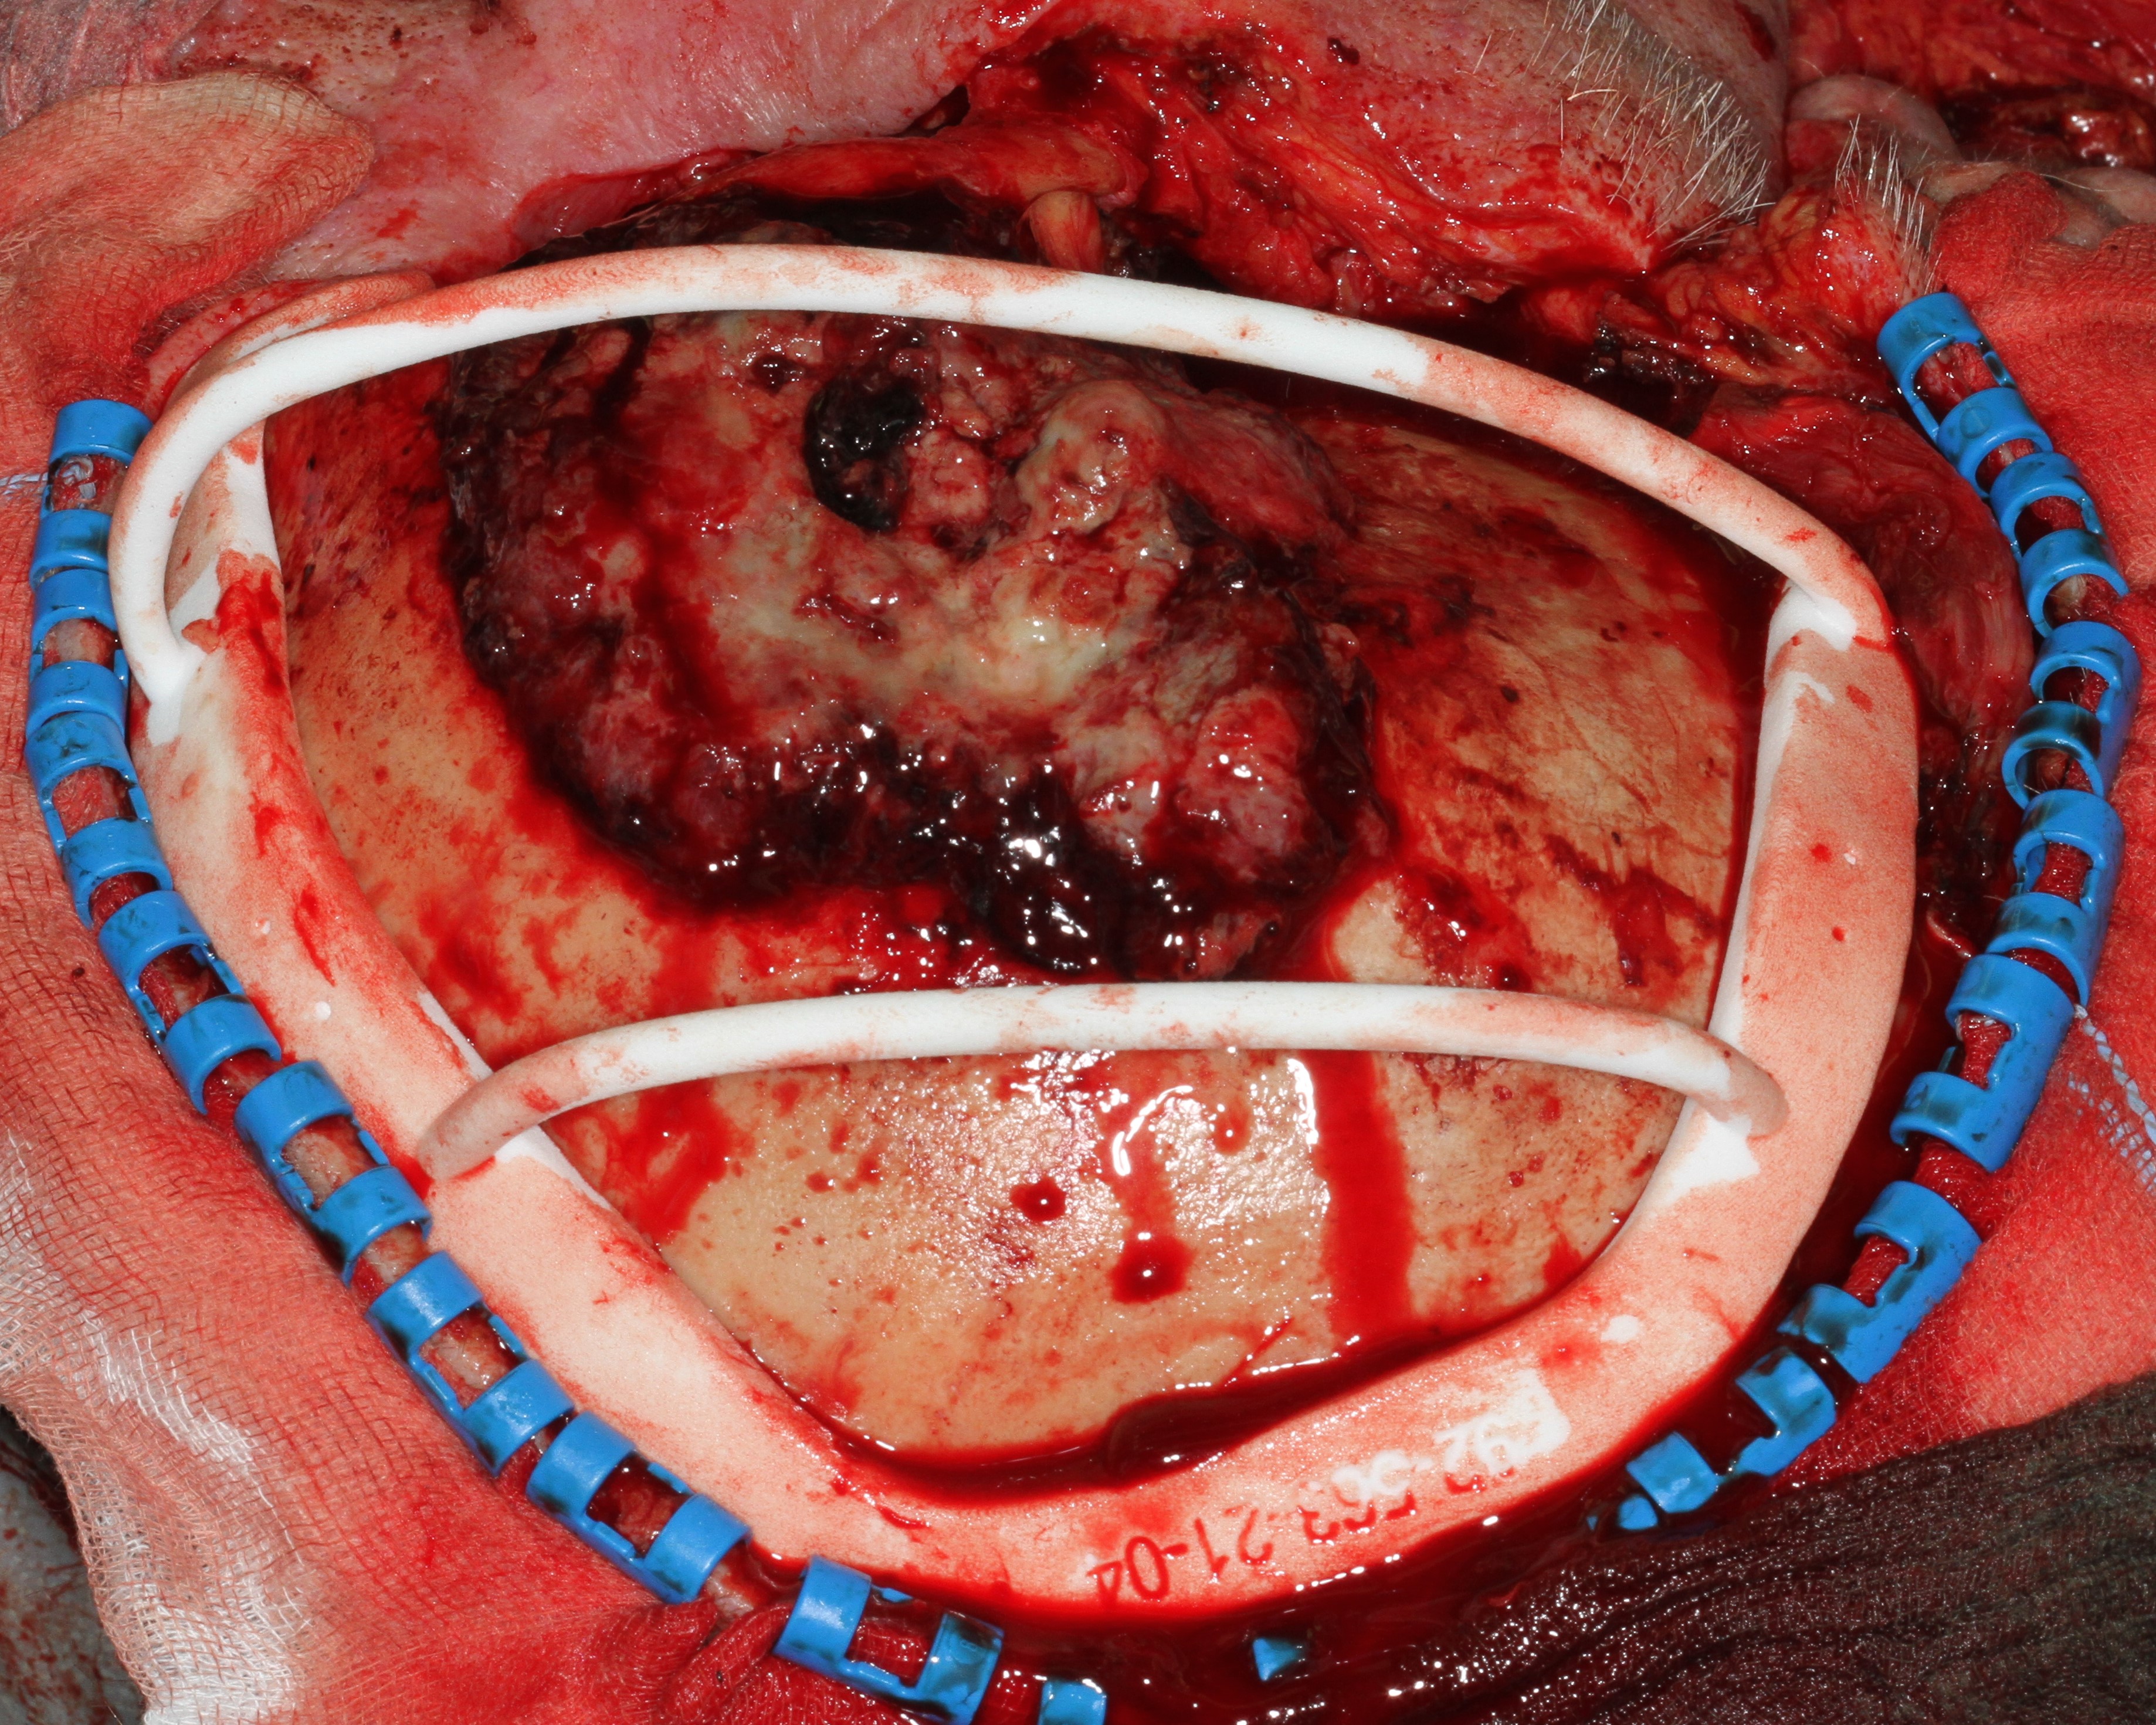

In cases of elective resection of the skull, for example in tumour surgery, a combination of resection guides and customised cranial implants can be helpful (Figure 11).

The removal of the affected part of the skull is planned based on a CT scan. To aid precise excision while minimising unnecessary bone loss, a resection guide is 3D printed from the high-resolution CT data. After resection along the resection guide, an implant exactly fitting into the defect is placed to protect the brain (Figure 12).

Figure 12: Cranial implant placed in the defect of the skull and fixed by screws.